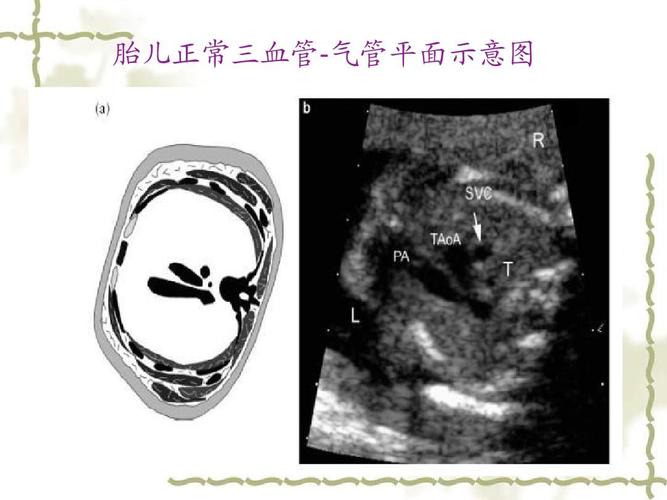

三血管气管切面示意图

三血管气管切面

三血管切面示意图